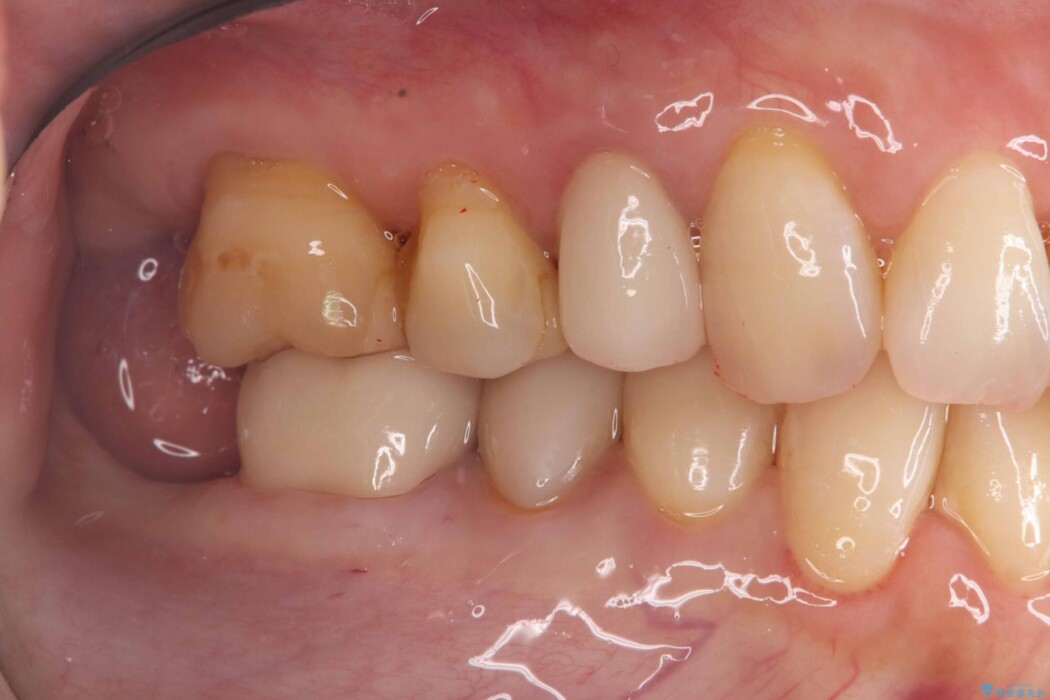

そのため今回は、歯をしっかり保護し、長期的な安定を図るために、オールセラミッククラウンによる修復を行いました。

クラウンにすることで、噛む力を分散しながら歯を保護できるため、再び割れてしまうリスクを大きく下げることが可能です。